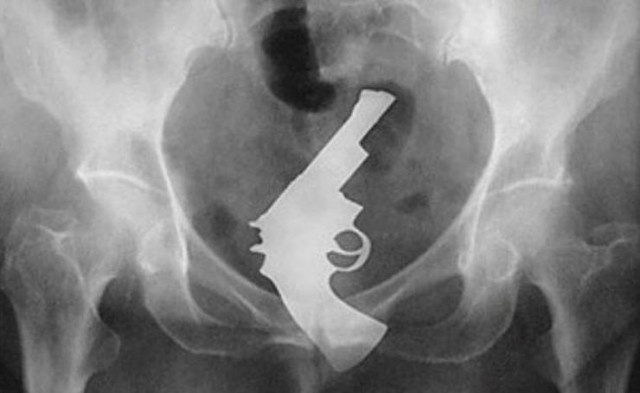

・股間以外のマグナム